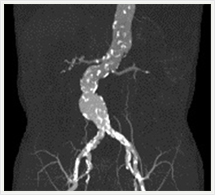

CTでは輪切り像の他にも立体的な画像(3D画像)を作成することもできます。そのためにはより細かくキレイな画像を撮影しなければなりません。当院では64列CTを導入しており、キレイな画像をより細かく撮影することができます。その画像を元に3D画像を作成することによって、より正確な手術のシミュレーションが可能になります。実際に手術をしたときの様子が、手術をする前に画像として見らます。外科系の手術には欠かせない技術となっておりますが、内科系でも血管内手術にも多く利用されております。

当診療放射線技術科では毎日各診療科に対して、その手術に最適な3D画像を提供しております。

以下にその3D画像を一部分紹介します。

腹部・腹部血管